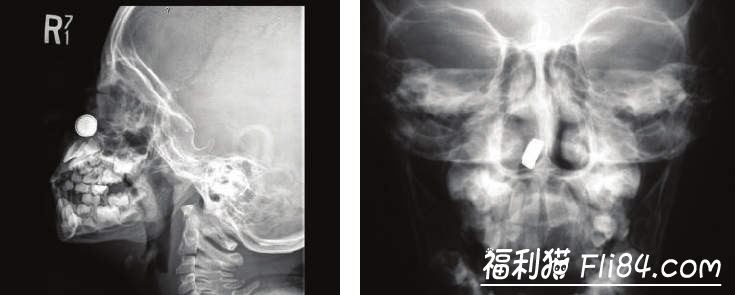

X光机下拍到的各种异物

耳朵・无线耳机・宝石・被小朋友塞入的细长玩具・衬衫上的钮扣或其他硬物・岩盐・莓果・为了挖耳屎反而卡进去的挖耳棒或钳子・体温计・珍珠・附在饮料上的吸管・微小芯片・装饰贝壳・梳子断掉的一小段尖端物・果冻或凝胶・塑胶蜘蛛・圣诞节装饰物

鼻子・磁铁・小型的贴纸・钮扣般大小的电池・粉笔・飞进鼻子里的虫・糖果包装纸・装饰品眼睛・驱虫球・葵花籽・圣诞节装饰物